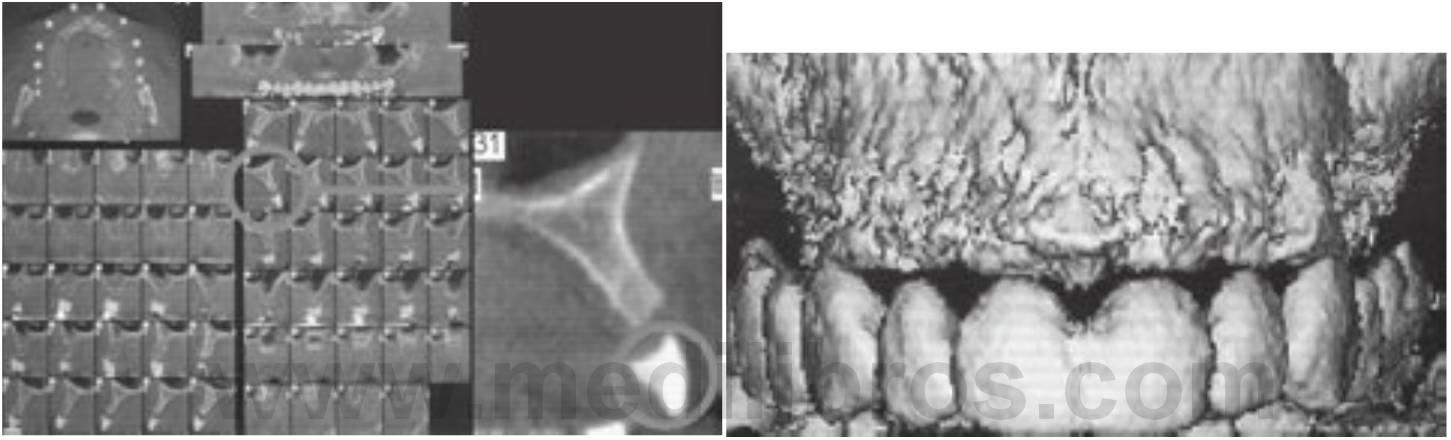

Las imágenes DentaScan proporcionan una reforma, organización e imagen en pantalla programadas del estudio de imágenes (fig. 3-10). El técnico o el radiólogo simplemente indica la curvatura del arco mandibular o maxilar, y el ordenador es programado para generar cortes de sección referenciados e imágenes tangenciales/panorámicas de los alveolos junto con imágenes tridimensionales del arco. Las imágenes de cortes transversales y panorámicos están espaciadas entre sí 1 mm y permiten una planificación del tratamiento prequirúrgico exacto.

Las limitaciones de las imágenes DentaScan incluyen imágenes que pueden no ser verdaderas en tamaño y requieran compensación de la magnificación, la determinación de la calidad ósea que requiere el empleo de ordenadores o estaciones de trabajo de imágenes, copias en soportes duros de imágenes DentaScan que solo incluyen una parte limitada de la escala de grises diagnóstica del estudio, y la inclinación de la cabeza del paciente durante el examen, lo que es crítico ya que todas las imágenes de corte de sección son perpendiculares al plano axial de la imagen. Esta técnica proporciona una información diagnóstica abundante que es exacta, detallada y específica. normalmente es necesaria una plantilla diagnóstica para aprovechar toda la ventaja de esta técnica. La plantilla diagnóstica permite al odontólogo incorporar el plan de tratamiento tridimensional del resultado protésico final al examen de las imágenes, evaluar la anatomía del paciente relacionada con los lechos implantológicos propuestos, la estética y la oclusión; y grabar y transmitir estos datos al paciente en el momento de la cirugía. La TC permite la identificación de la enfermedad, la determinación de cantidad y calidad óseas, la identificación de las estructuras críticas en las regiones propuestas, y la determinación de la posición y orientación de los implantes dentales. Por ello, la TC es capaz de determinar los cinco objetivos radiológicos de las imágenes implantológicas prequirúrgicas (cuadro 3-10; v. cuadro 3-2).

Uno de los adelantos más significativos en la TC es la TCI interactiva, que dirige muchas de las limitaciones de la TC. La TCI es una técnica que se desarrolló para crear un puente sobre la separación existente en la transferencia de información entre el radiólogo y el clínico. Esta técnica permite al radiólogo transferir el estudio de imagen al clínico como un archivo de ordenador que le permite observar e interaccionar sobre el estudio de imagen con un ordenador personal. El ordenador del odontólogo se transforma en una estación de trabajo radiológica diagnóstica con herramientas para medir la longitud y anchura de los alveolos, medir la calidad ósea, y cambiar la ventana y nivel de la escala de grises del estudio para aumentar la percepción de las estructuras críticas. Se proyectan y referencian imágenes axiales, cortes de sección, panorámicas, y tridimensionales de manera que el odontólogo puede apreciar la misma posición o región de la anatomía del paciente en cada una de las imágenes. Se pueden seleccionar regiones de la anatomía del paciente para proyectarlas normalmente, con magnificación, o con un número de representaciones de escala de grises que faciliten la apreciación de la anatomía, de las estructuras o de la enfermedad.

Una característica importante de la TCI es que el odontólogo y el radiólogo pueden llevar a cabo cirugía electrónica (CE) seleccionando y colocando cilindros de tamaño arbitrario que simulan la forma de la raíz de los implantes en las imágenes. Con una plantilla diagnóstica adecuadamente diseñada la CE puede llevarse a cabo para desarrollar electrónicamente la planificación del tratamiento del paciente en tres dimensiones. Los implantes electrónicos pueden colocarse en posiciones y orientaciones arbitrarias unos respecto de los otros, de los alveolos, de las estructuras críticas, y de la oclusión prospectiva y de la estética. La cirugía electrónica y la TCI permiten el desarrollo de una planificación de tratamiento en tres dimensiones que se integra en la anatomía del paciente y puede ser visualizado antes de la cirugía por miembros del equipo implantológico y el paciente para su aprobación o modificación. La TCI permite la determinación de la calidad ósea adyacente a los lechos implantológicos prospectivos (figs. 3-14 a 3-16). Una vez determinados con exactitud el número y tamaño de los implantes, junto con la densidad ósea en los sitios implantológicos propuestos, el odontólogo puede determinar con exactitud las características de los implantes antes de la cirugía.

El primer paso en el procedimiento de la TCI son las impresiones para los modelos de estudio. Con el empleo de estos modelos, se completa un encerado diagnóstico de acuerdo con la posición ideal de los dientes ausentes en cuestión haciendo énfasis en la prótesis final. Partiendo del encerado diagnóstico, se fabrica una plantilla radiopaca que el paciente llevará durante el escaneo. Esta plantilla diagnóstica permitirá transferir el posicionamiento ideal de los dientes al examen radiográfico.